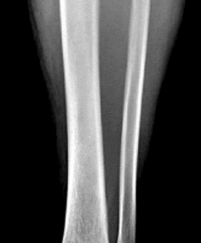

Question 39:

A 28-year-old male is treated with intramedullary nailing for a closed, comminuted midshaft tibial fracture. Twelve hours post-operatively, he complains of severe leg pain out of proportion to the injury, unrelieved by intravenous opioids. Passive stretch of the toes elicits excruciating pain. Compartment pressure monitoring reveals an absolute compartment pressure of 35 mmHg, and his blood pressure is 110/60 mmHg. What is the most appropriate next step in management?

Correct Answer: Immediate four-compartment fasciotomy of the leg

Explanation:

The diagnosis is acute compartment syndrome. The critical threshold for intervention is the delta pressure (Diastolic Blood Pressure - Absolute Compartment Pressure). In this patient, the delta pressure is 60 - 35 = 25 mmHg. A delta pressure of less than 30 mmHg represents inadequate tissue perfusion pressure and is a strict indication for emergent fasciotomy (four-compartment in the leg). Elevating the leg above the level of the heart is contraindicated as it further decreases arterial inflow and worsens tissue ischemia.